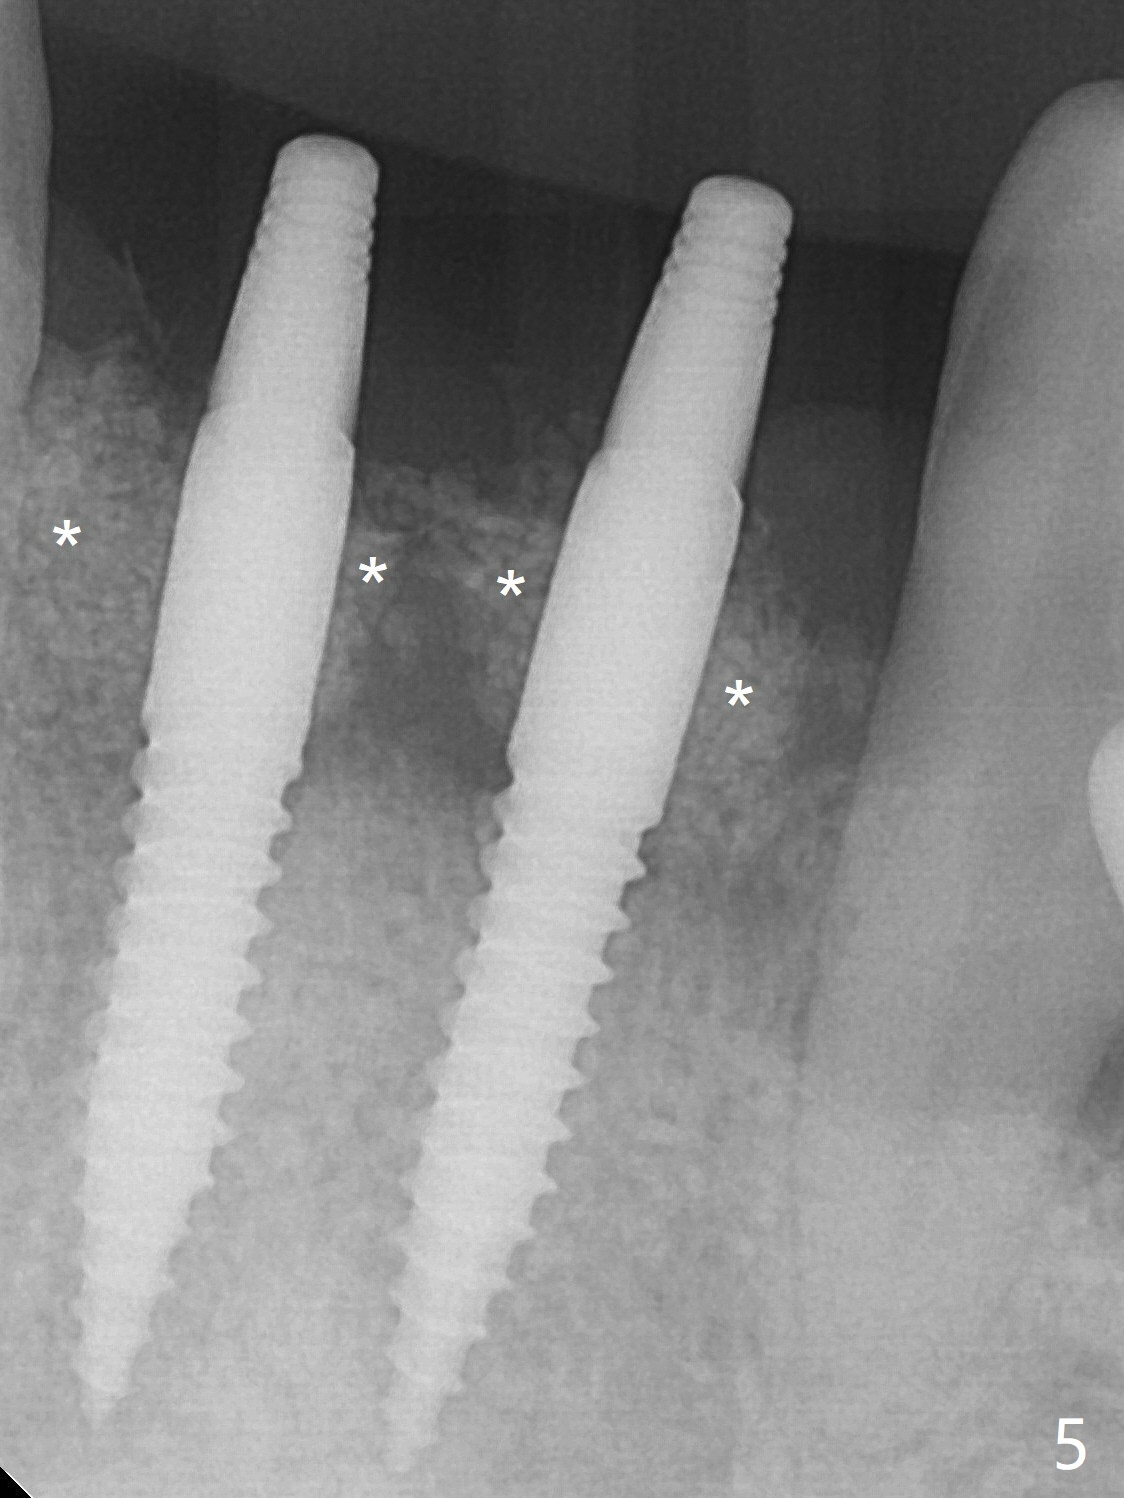

When dummy implants are placed partially, there is a large bony defect (Fig.4 *). After final implants (3x14(4) mm) are placed, allograft is placed coronally (Fig.5 *). Hard tissue heals 5.5 months postop (Fig.10 with formation of apparent bony trabeculae: *).